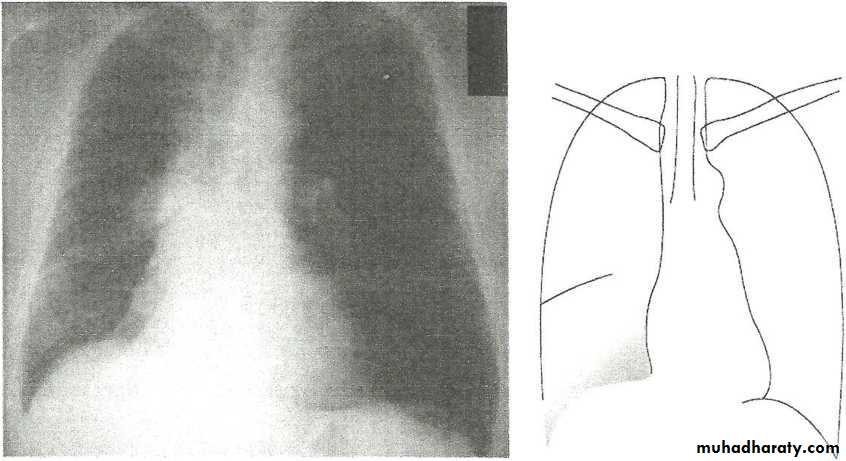

Pleural Effusion on Chest Radiographs.

Posteroanterior (A) and lateral (B) chest radiographs demonstrate the typical meniscoid appearance (arrows) in a patient with a left pleural effusion

Encapsulated fluid

(A) PA and (B) lateral chest radiographs. Pleural fluid is encapsulated in the major fissure and against the anterior chest wall. These encysted fluid collections can mimic a lung tumour.